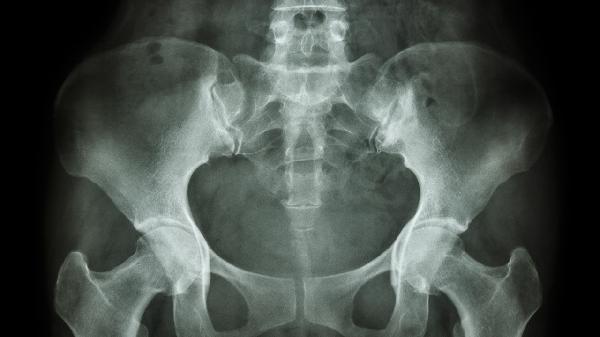

极少数患者存在骨盆发育异常或胶原蛋白合成障碍,导致耻骨联合稳定性先天不足。这类情况多在青春期骨骼快速生长时显现,可能伴随其他关节松弛症状。需通过影像学评估后制定个性化康复方案。

日常应注意避免久站久坐,睡眠时在两膝间放置枕头减轻骨盆压力。建议选择软底鞋减少行走震动,产后女性可进行专业的盆底肌训练。饮食上适当增加牛奶、豆腐等含钙食物,肥胖者需控制体重以降低骨盆负荷。若疼痛持续加重或出现步态异常,应及时进行骨盆X光或MRI检查。